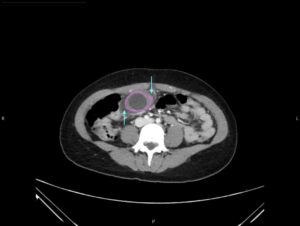

Hydropic Gallbladder. CT, Axial, Annotated. JETem 2025

Hydropic Gallbladder. CT Axial Annotated. JETem 2025